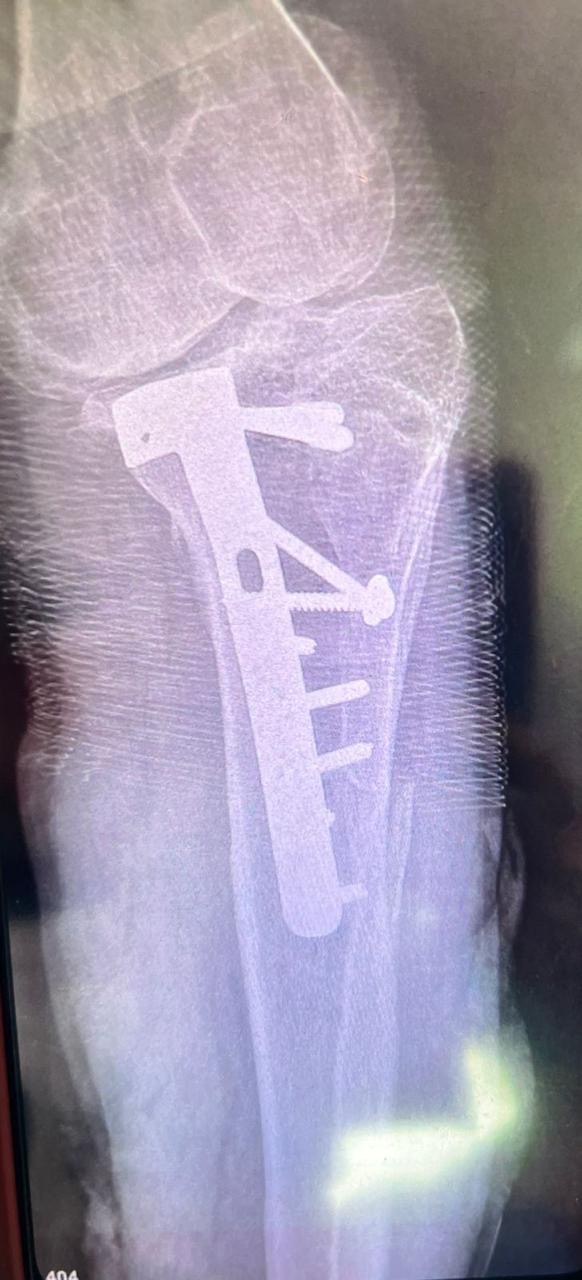

• Además, ya tenía una prótesis con tornillos en esa pierna que ha sido afectada nuevamente

Adjuntamos radiografías, informes médicos y un estimado del coste total para garantizar total transparencia. Iremos informando paso a paso sobre su evolución y cada procedimiento realizado.

• In addition, he already had a prosthesis with screws on that leg that has been affected again

We attach x-rays, medical reports and an estimate of the total cost to guarantee total transparency. We will inform you step by step about its evolution and each procedure carried out.